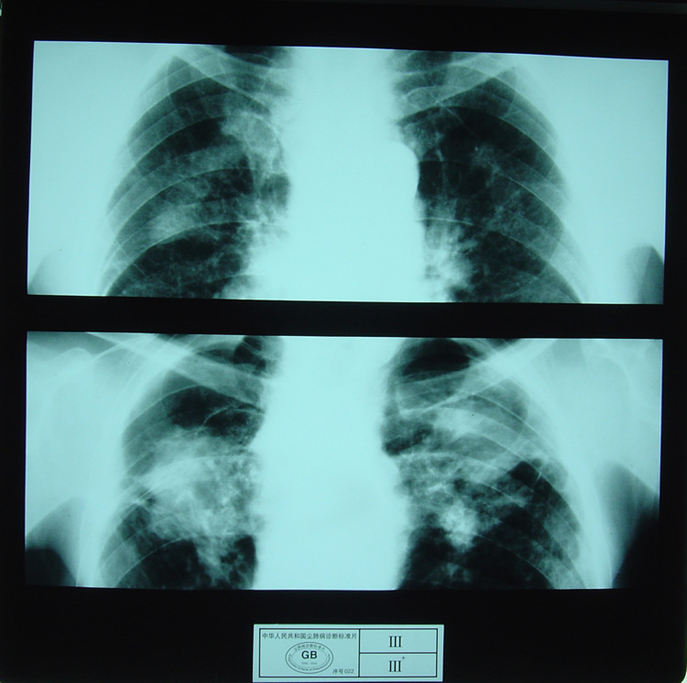

3)大阴影:在X射线胸片上,肺野内直径或宽度超过10mm的阴影,为晚期矽肺的重要X射线表现,形状有长条形、圆形、椭圆形、或不规则形,病理基础是团块状纤维化。大阴影的发展可由圆形小阴影增多、聚集,或不规则小阴影增粗、靠拢、重叠形成;多在两肺上区出现,逐渐融合成边缘较清楚、密度均匀一致的大阴影,常对称,形态多样,呈八字形等,也有先在一侧出现;大阴影周围一般有肺气肿带的X射线表现。

大阴影

3)尘肺叁期:有下列表现之一者:

a) 有大阴影出现,其长径不小于20mm,短径不小于10mm;

b)有总体密集度为3级的小阴影,分布范围超过4个肺区并有小阴影聚集;

c) 有总体密集度为3级的小阴影,分布范围超过4个肺区并有大阴影。

尘肺叁期

尘肺叁期

尘肺叁期